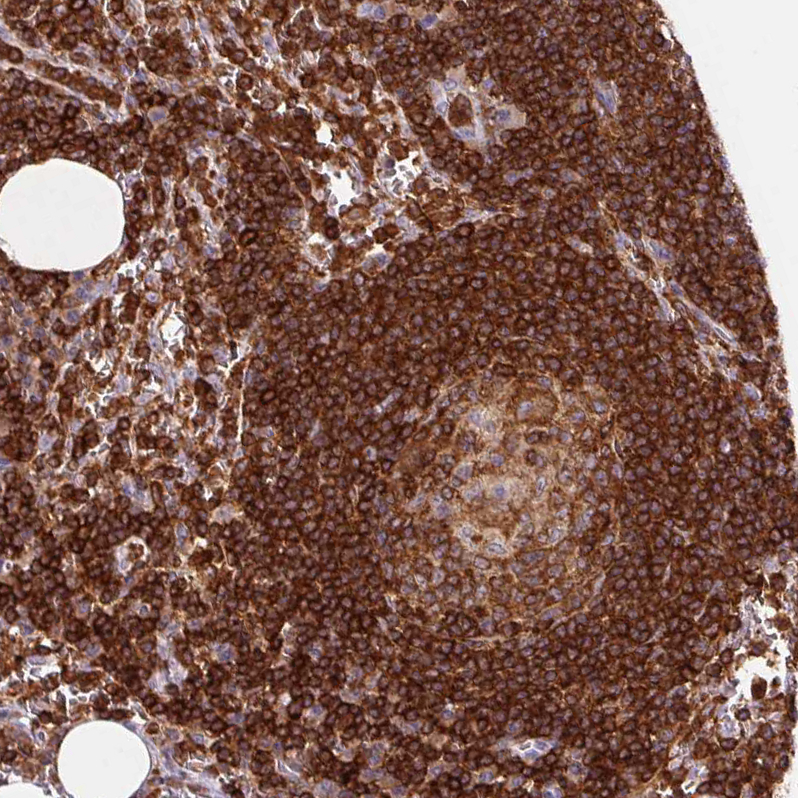

Immunohistochemistry analysis in human lymph node and heart muscle tissues using HPA063903 antibody. Corresponding APBB1IP RNA-seq data are presented for the same tissues.